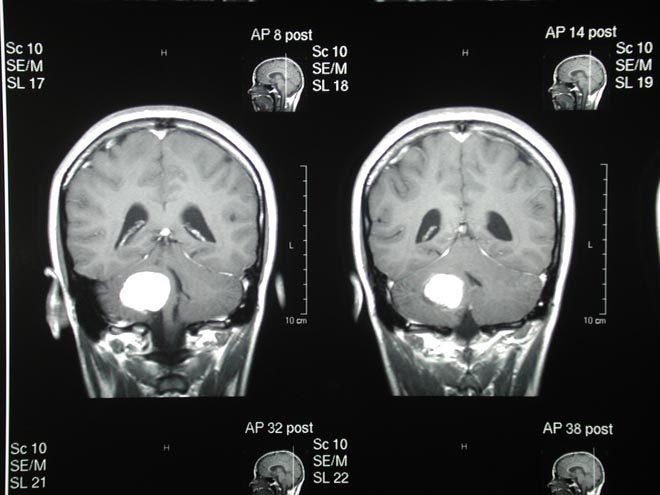

Cuando las nanopartículas se adhieren es posible verlas a través de tres formas de imágenes, para hacer la operación de manera detallada. La primera es por medio de resonancia electromagnética que permite ver la ubicación del tumor en la cirugía.

La segunda es la imagen fotoacústica, que es un método que usa pulsos de luz que son absorbidos por las nanopartículas y que hace que se calienten. Esto crea un ultrasonido que proyecta una imagen tridimensional del tumor.

La tercera se llama imagen Raman, que hace que las nanopartículas irradien cantidades muy pequeñas de luz en ciertas situaciones. Eso le permite al cirujano distinguir totalmente entre el tumor y el tejido sano.